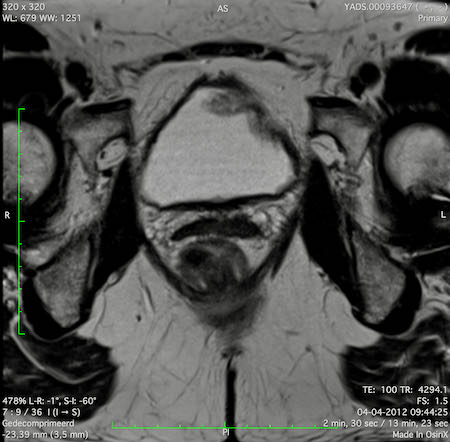

Hình ảnh

Các hình ảnh được cung cấp cho thấy ung thư biểu mô tế bào nhẫn với tình trạng dày lan tỏa thành trực tràng, hình ảnh bia bắn điển hình, và sự xâm lấn mỡ mạc treo trực tràng.